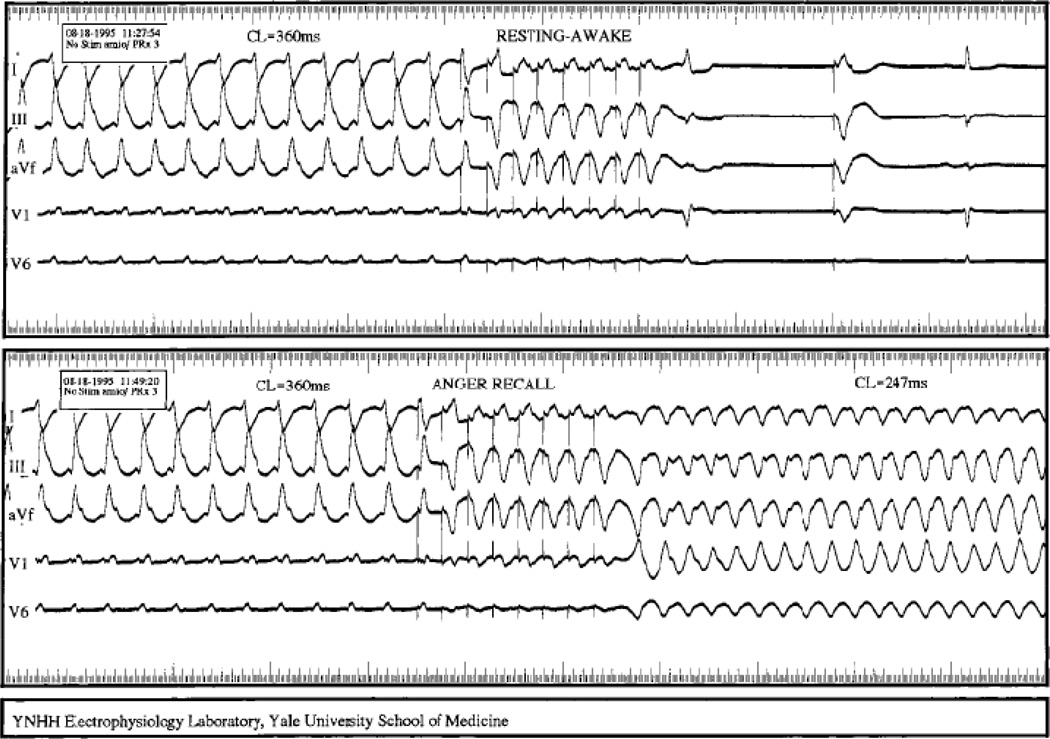

In a landmark study published in 1973,[33] Lown investigated the possibility that mental stress could facilitate induction of ventricular arrhythmias. Using a protocol conceptually similar to electrophysiologic programmed stimulation in a dog model, he found that in rested animals, only 1 PVC could be induced, and required a high output of 35 mA. In a dog stressed by being lifted in a sling conditioned to be a noxious experience, 2 PVCs were induced, using just 5mA. (figure 5.) In a similar study in humans, we later evaluated the effects of mental stress on induced arrhythmias in patients with a history of known ventricular arrhythmias and ICDs.[34] All patients had had VT which was terminated with anti-tachycardia pacing at previous EP studies. Some patients had VT induced earlier in the protocol, using fewer extra-stimuli, although this was not significant. However, arrhythmias induced during mental stress were faster than those induced at rest, and were harder to terminate. In some cases, an identical VT which had been pacer-terminated in the baseline state required shock for termination during anger-recall, (figure 6) suggesting that autonomic changes due to the anger had altered properties of conduction and refractoriness of the VT circuit, eliminating the excitable gap. Further understanding of the electrophysiological underpinnings of stress-induced arrhythmogenesis is an important avenue of future research. It will also be important to investigate whether there are interactions between gender and stress in impacting ventricular arrhythmias. As in most defibrillator studies, women are under-represented in all the above studies.

Figure 6. Alteration of VT termination by anger.

Top, in the resting-awake stae, VT of CL 360ms is induced and terminated by ATP.

Bottom, During anger recall, an identical VT is induced but is accelerated by ATP into a zone requiring shock.

From Lampert, Circulation 2000, (ref 26), with permission